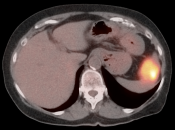

Recurrence, Restaging & Surveillance:

- PET/CT is utilized for patients with known or suspected recurrent disease (or at high risk for recurrence).

- Distinguishing recurrence from post-therapeutic inflammation.

Assessing Response to Therapy & Prognosis: Assess success or failure of therapy, and ultimate outcome/prognosis.

Metastatic Disease:

- Direct invasion of adjacent structures.

- Lymphatic spread to pelvic and retroperitoneal lymph nodes.

- Hematogenous spread, often to lungs, liver, and bone.